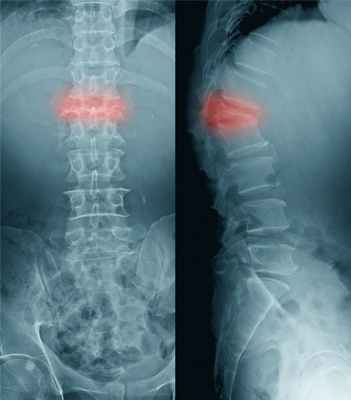

Компрессионные переломы

Признаки: Боль в спине по средней линии, которая иногда начинается внезапно. Обычно у людей старшего возраста или больных с остеопорозом.

Если перелом возникает в результате сжатия тела позвонка, то он носит название компрессионного.

У лиц старшего возраста такой перелом возможен из-за остеопороза, который чаще встречается у женщин. К компрессионному перелому, иногда даже при минимальной внешней нагрузке, приводит поражение позвоночника при метастазировании злокачественных опухолей.